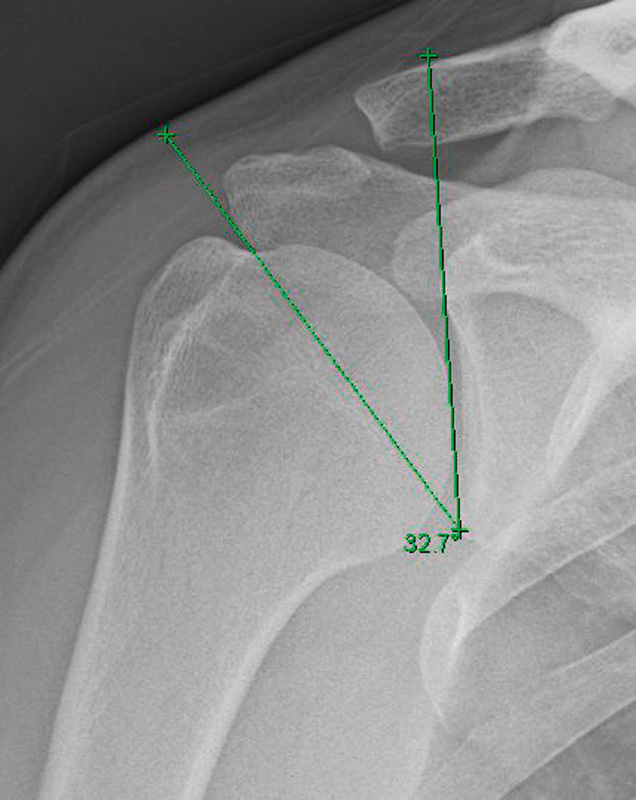

Para evaluar estas fuerzas, Moor(6) describió el ángulo crítico del hombro (Figura 1), que es una medida radiológica que está formada por una línea que conecta el margen inferior y el margen superior de la cavidad glenoidea y otra línea que une el margen inferior de la glenoides con el borde lateral del acromion, cuya ventaja es que combina la extensión lateral del acromion con la inclinación de la fosa glenoidea en una única medida cuantificable. De manera que las cifras > 35° se relacionaron con el aumento del riesgo de lesión no traumática del manguito rotador y valores < 30° con artrosis glenohumeral.

Figura 1. Radiografía con proyección anteroposterior verdadera de hombro derecho. Medición del ángulo crítico del hombro (32,7°).

Se trata del predictor anatómico más potente de roturas degenerativas del manguito, de entre los parámetros radiológicos más estudiados (índice acromial, ángulo lateral del acromion, pendiente acromial, morfología acromial de Bigliani, etc.)(12,13). Este ángulo presenta una concordancia interobservador excelente(13) y es un predictor potente y sensible de roturas degenerativas tanto parciales como totales debido a que toma en cuenta ambos parámetros y a que son fácilmente medibles con exactitud en la radiografía(14,15) y tomografía computarizada(16), siendo más fiable que la medida obtenida mediante resonancia magnética (RM)(17). Sin embargo, es importante realizar una proyección anteroposterior (AP) verdadera de hombro, ya que se ha demostrado que desviaciones mayores de 5° en la anteversión pueden resultar en más de 2° de diferencia en el valor del ángulo crítico(15).